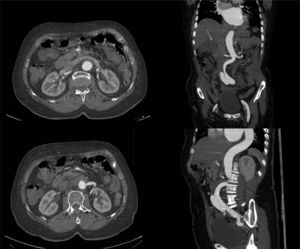

En este artículo presentamos un caso de una DA espontánea aguda de aorta abdominal infrarrenal asociada a un aneurisma de aorta abdominal, y que se intervino de forma quirúrgica en diciembre de 2013. La paciente en cuestión es una mujer de 72 años, hipertensa (HTA), dislipémica, con fibrilación auricular anticoagulada con «davigatrán», cardiopatía hipertensiva con una fracción de eyección conservada y una insuficiencia aórtica leve-moderada. La mujer acudió a urgencias por un cuadro de 9 días de evolución de dolor lumbar inespecífico, por lo que fue dada de alta con tratamiento analgésico ante la sospecha de cólico nefrítico. Debido a la persistencia del dolor, y a pesar del tratamiento, acudió al cabo de un día, de nuevo, a urgencias donde se realizó angio-TAC que objetivó una DA aguda a nivel abdominal infrarrenal con un AAA de 37mm, con falsa luz, que llega a nivel proximal a la altura del tronco celíaco sin englobar ninguna arteria visceral. Distalmente, la luz falsa progresa sin trombosis a las arterias ilíacas (fig. 1). La paciente se encontraba hemodinámicamente estable, y a la exploración física presentaba pulsos distales y exploración abdominal anodina. Ante los hallazgos radiológicos se decidió realizar cirugía abierta urgente mediante bypass aorto-bifemoral con clampaje suprarrenal y reimplante de la arteria renal izquierda, previa instilación de suero Ringer frío en ambos riñones. En la intervención se fijó la capa íntima en todas las anastomosis (fig. 2A-C).

Angio-TC: Aneurisma de aorta abdominal infrarrenal de 37mm con disección aguda, que progresa distalmente con ambas luces permeables hasta arterias ilíacas externas, y progresa proximalmente con falsa luz trombosada hasta nivel del tronco celíaco. No se observa disección a nivel de aorta torácica, cuyo diámetro a nivel distal es de 33,7mm.